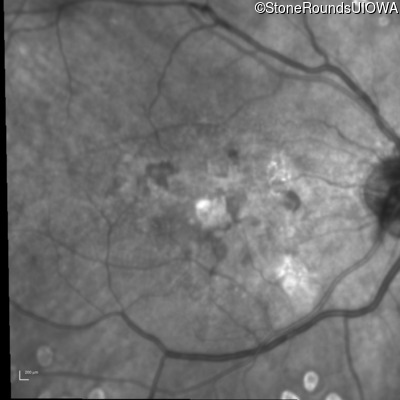

History

This 43 year old woman has experienced a gradual reduction in her central vision for the past 3 years.

Diagnosis & molecular findings

| Disease | Gene | Allele 1 variant(s) | Allele 2 variant(s) | Inheritance mode |

|---|---|---|---|---|

| Malattia Leventinese | EFEMP1 | Arg345Trp CGG>TGG | AD |